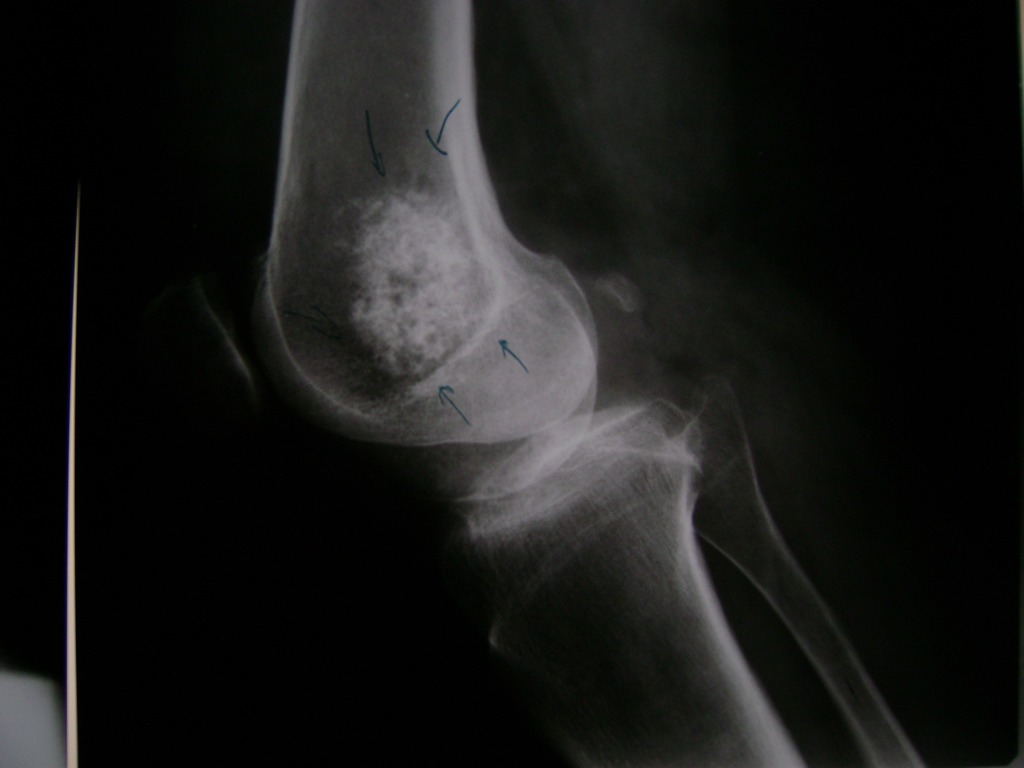

Fémur - Rodilla